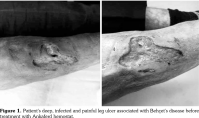

A 50-year-old male patient presented with a non-healing leg ulcer for about one year. He had a past medical history of BD diagnosed at age 29 and therapy was started. During this period, his ulcers in oral and genital area continued to occur frequently. He was diagnosed as BD with recurrent oral, genital ulcers and positive pathergy test.[10] The patient was treated with oral prednisolone (32 mg/day) and colchicine (2 mg/day) after the diagnosis. Oral and genital ulcers relatively improved. A leg ulcer occurred in his right leg after wearing an anti-varicose bandage one year before. For about one year, the leg ulcer did not respond to conventional immunosuppressive therapy (such as prednisolone, azathioprine, cyclosporine, methotrexate, mycophenolate mofetil, rituximab) or tumor necrosis factor (TNF) inhibitors (infliximab). The patient underwent surgical treatment for the leg ulcer and hyperbaric oxygen therapy was applied for his wound. The patient's leg ulcer did not respond to those treatments. When admitted to the general surgery outpatient clinic at age 50, his right lower deep leg ulcers were located between the knee and ankle (Figure 1). His leg ulcer was painful, deep and irregular margined about 10x10 cm. Laboratory studies revealed a white blood cell count of 7.3x103 /μL, hemoglobin level of 10.1 g/dL and platelet count was 317x103/μL. Serum C-reactive protein was 1.92 mg/dL and sedimentation was 11 mm/hour. A written informed consent was obtained from the patient.

Based upon the patient’s clinical history, characterized by persistence and exacerbation of leg ulcers, and poor response to conventional treatment, we decided to administer topical ABS on his leg ulcer. The patient provided informed consent to receive the ABS local therapy. ABS was applied to the patient's ulcer daily. One month after initiating local ABS treatment, the right leg ulcer was markedly improved (Figure 2). After two months, the ulcer continued to improve. There was no adverse event due to the topical utilization of ABS.